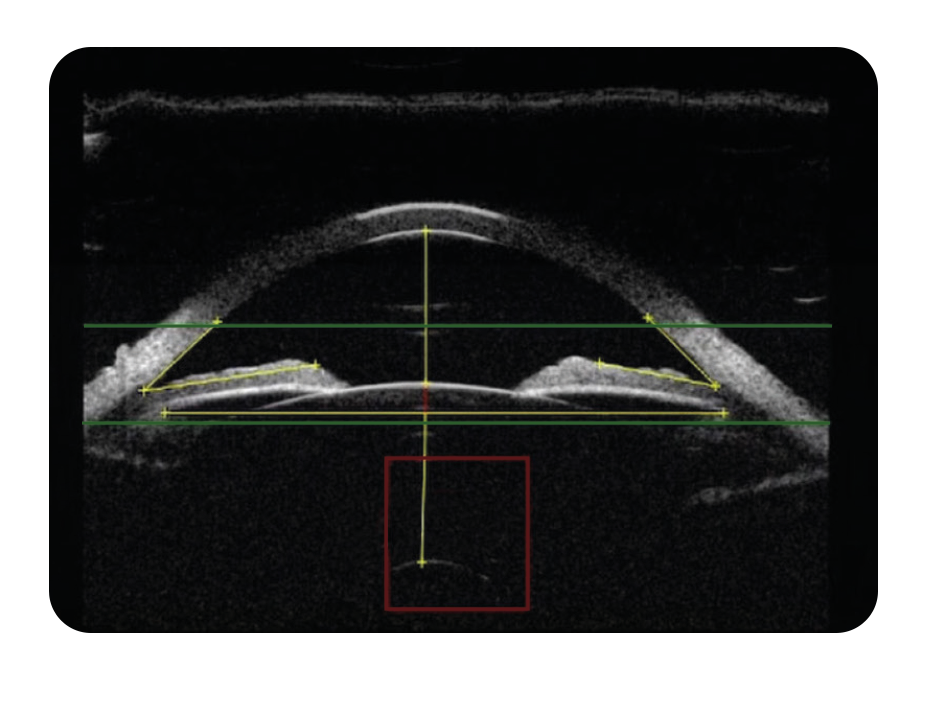

ABSolu® UBM: Direct Access to the Sulcus-to-Sulcus (STS)

The ABSolu® 50 MHz Linear Probe Ultrasound Biomicroscope (UBM) addresses the limitations of optical devices by directly imaging the entire anterior segment, including the Sulcus-to-Sulcus (STS) diameter. This internal measurement is far more predictive of vault behavior and allows surgeons to build a precise understanding of each eye’s anatomy.